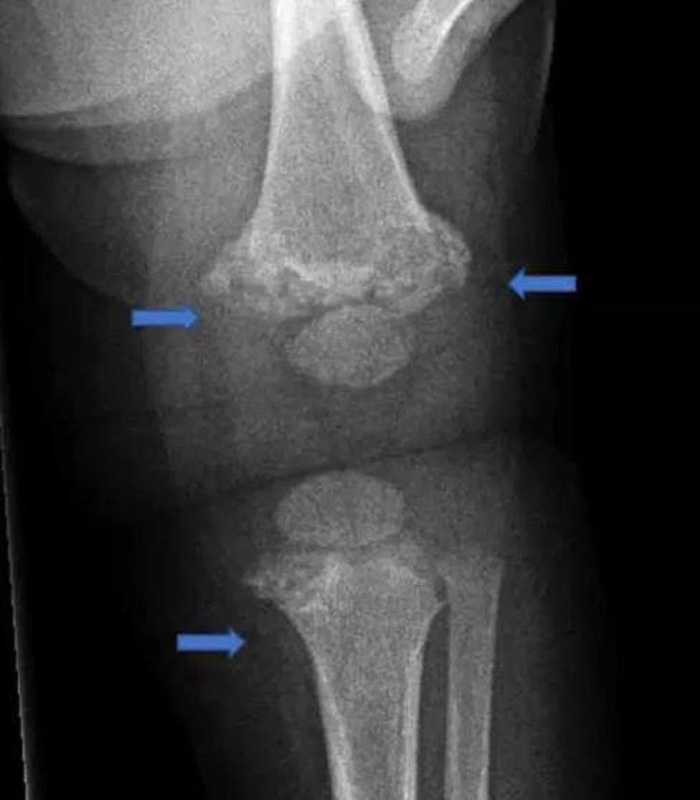

据英国《太阳报》报道,32岁男子建卓札克与22岁妻子柯宾丝卡,在2017年时把年仅4个月大的儿子送到医院,全身是伤。医师检查后认为状况有异,夫妻俩则直呼孩子是被边缘翘起来的地毯绊倒,但医师发现,孩子身上共有28处骨折,而且伤势相当严重,包括手臂、肋骨、膝盖、脚踝等几乎都是全断的状况。医师验伤认为,男婴遭到强大的外力冲击,因此报警处理,建卓札克和柯宾丝卡随后遭到警方逮捕。

男婴膝盖骨整个断开。